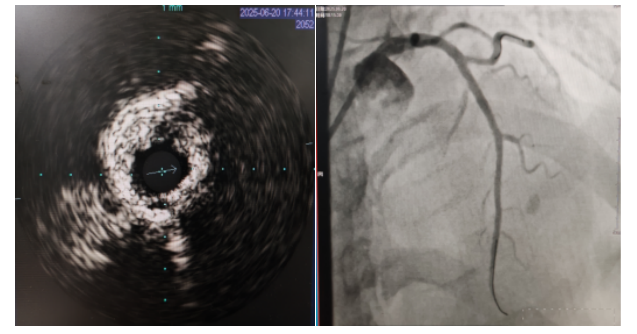

術(shù)中,趙慶禧主任醫(yī)師、雷剛副主任醫(yī)師運用IVUS血管內(nèi)超聲技術(shù)評估,發(fā)現(xiàn)患者前降支、對角支0.1.1型真性分叉病變,前降支近中段嚴重鈣化、成角并99%狹窄,對角支近段嚴重鈣化并99%狹窄,傳統(tǒng)冠狀動脈旋磨術(shù)容易引起冠狀動脈穿孔,決定采用沖擊波球囊技術(shù)即血管內(nèi)沖擊波鈣化碎裂術(shù)對患者嚴重鈣化的血管進行介入治療。通過球囊低壓擴張,向血管病變處發(fā)射非聚焦、低能量、脈沖式的沖擊波,對前降支及對角支進行了連續(xù)5個周期沖擊波脈沖治療,安全地碎裂淺、深層鈣化,原本看似堅不可摧的環(huán)形鈣化區(qū)逐漸顯現(xiàn)出了裂痕,多處關(guān)鍵位置發(fā)生了斷裂,充分預處理后于前降支近中段串聯(lián)植入支架3枚,對角支植入藥物球囊,術(shù)后造影見血管病變處狹窄完全消失,支架膨脹完全,貼壁良好,各項生命體征平穩(wěn),手術(shù)非常成功,患者返回心血管內(nèi)科病房繼續(xù)治療,并于4天后順利出院。